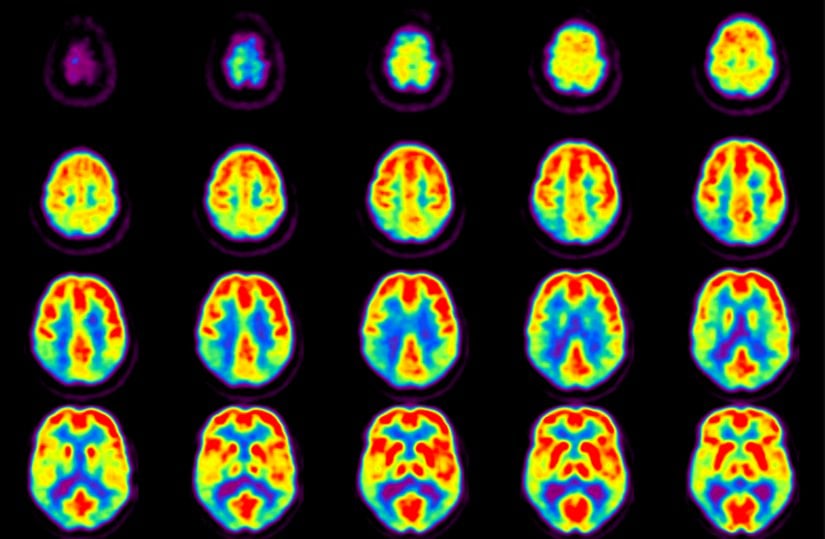

Beyin ve Merkezi Sinir Sistemi Hastalıkları

Glikoz, beynin en temel yakıtıdır. PET taramaları için hazırlanan ilaçlardaki izleyiciler, glikoz ve benzeri bileşiklere tutturulur. Bu şekilde tarayıcı, radyoaktif glikozu görüntüleyerek beynin en fazla oranda glikoz kullandığı bölgeleri tespit eder.

PET taramasının teşhis ve tedavisinde kullanıldığı bazı merkezi sinir sistemi hastalıkları şunlardır:

- Beyin tümörleri

- Alzheimer hastalığı

- Epilepsi

- Parkinson hastalığı

- Depresyon

- Kafa travması